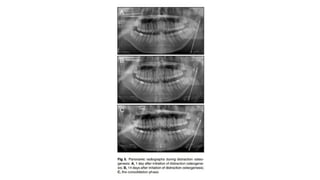

Cephalograms and panoramic radiographs during distraction, and intraoral photographs after

distraction. (A) During advancement. (B) After advancement © ) 2 months after advancement.